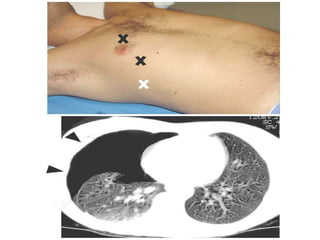

Notice the increased lucency of the cardiophrenic sulci in this patient

with inferior anteromedial pneumothoraces. A CT scan confirms the

Notice the increasedlucency of the cardiophrenic sulci in this patient with inferior anteromedial pneumothoraces. A CT scan confirms the diagnosis

• 44.

 a hyperlucentupper quadrant with visualization of the superior surface of the diaphragm and visualization of the inferiorvena cava.  double-diaphragm sign

• 45.

 Antero lateralair may increase the radiolucency at the costo phrenicsulcus. This is called the deep sulcus sign.